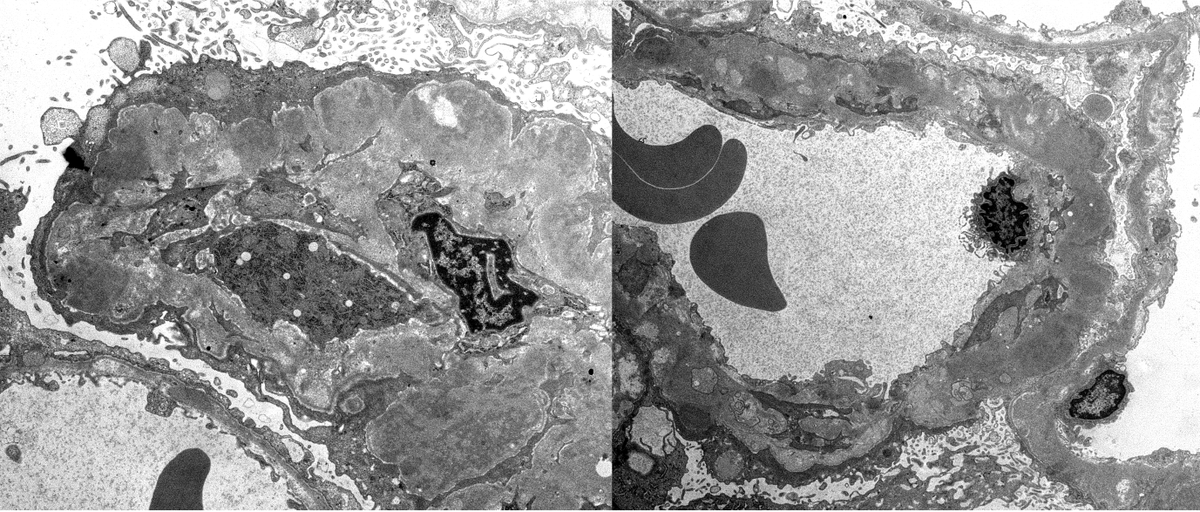

Teenager with nephrotic syndrome. Biopsy revealed unusual case of membranous nephropathy in a peds patient. PLA2R positive (IHC). PLA2R most common antigen in peds MN. EXT2 also common, SEMA3B less common. ( https://t.co/zEASwdQXIe)

#renalpath #pathsky #nephsky